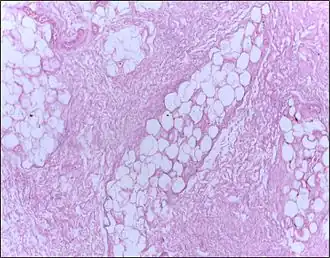

![]() Micrografía de tejido mamario que muestra necrosis grasa. Tinción Hematoxilina-Eosina | ||

La necrosis grasa es una forma de necrosis caracterizada por la acción de enzimas digestivos sobre la grasa.[1]

En la necrosis grasa el enzima lipasa libera ácidos grasos de triglicéridos. Entonces, los ácidos grasos se combinan con calcio para formar jabones. Estos jabones aparecen como depósitos calcáreos blancos.[2]

Normalmente está asociado con trauma del páncreas o pancreatitis aguda.[2][3] También puede ocurrir las mamas,[4] las glándulas salivales[5] y en neonatos después de un parto traumático.[cita requerida]